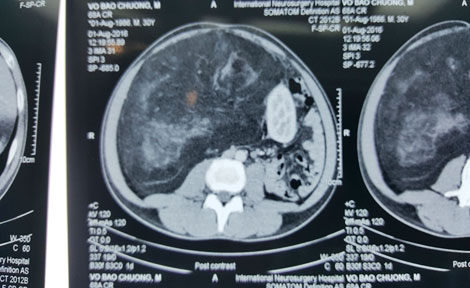

| Hình chụp CT cho thấy các khối bướu lớn chiếm trọn ổ bụng và chèn ép các cơ quan nội tạng khác. |

Qua phim chụp CT, các bác sĩ thấy một khối bướu chiếm trọn vùng bụng bên phải. Đặc biệt, do khối bướu quá to nên đã đẩy quả thận trái sang hẳn bên phải, khiến cho bệnh nhân này thoạt đầu giống như có hai quả thận ở bên phải. Sau khi xem xét kỹ các yếu tố cơ bản, bệnh nhân được các bác sĩ chỉ định phẫu thuật. Ca phẫu thuật diễn ra vào ngày 1/9 thuận lợi do các bác sĩ đã có kinh nghiệm từ ca phẫu thuật của bệnh nhân đầu tiên; khối bướu lấy ra có diện tích 53x35cm, nặng 7,3kg. Bệnh nhân ổn định và được xuất viện 4 ngày sau đó.